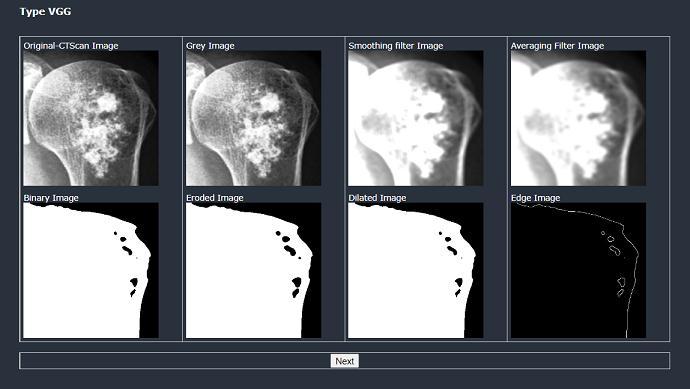

The discussion of results is that same image is taken as inputforbothAlexNetandVGG16andeventuallyitcanbe concludedthatwhichmethodhasgoodaccuracy.

Figure 2: Preparation steps in AlexNet for Stage 0 Figure 3: Preparation steps in VGG16 for Stage 0 2 and Figure 3 depicts the preparation steps before the classification. The result is classified as non cancerous. The accuracy for AlexNet is 88.34% and forVGG16is99.995%. Figure 4: Preparing steps in AlexNet for Stage 1 Figure 5: Preparing steps in VGG16 for Stage 1 4andFigure5depictsthepreparationstepsbefore the classification. The results of this step is same in both VGG16andAlexNet. Figure 6: Result in AlexNet for Stage1 Figure 7: Result in VGG16 for Stage1